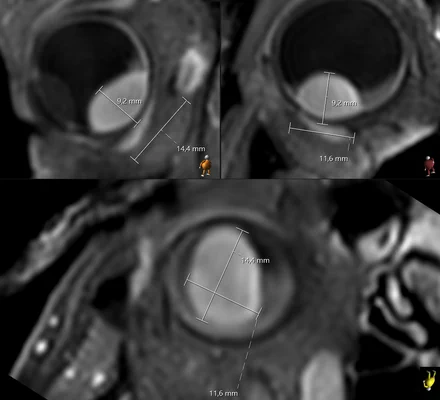

The isotropic resolution allows for accurate 3D assessment of the lesion dimensions.